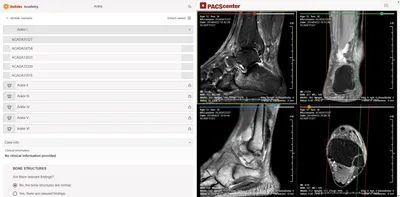

Our Radiology Reporting Simulator delivers an innovative e-learning experience that mirrors the reporting clinical practice of radiologists. Designed for practising professionals, this advanced simulator lets you practice reporting on real, anonymous MRI or CT cases directly in your browser.